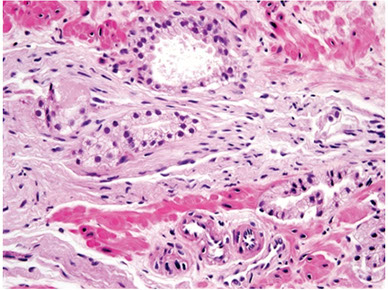

Benign prostate c corpora amylacea

Benign Prostatic Hyperplasia (BPH)

aka nodular hyperplasia, MC urologic dz in men

The smallest nodules are have loose mesenchyme and prominent small round vessels

- glandular part made of small and large acini, some c papillary infoldings and projections c central fibrovascualr core (not a specific finding)

- stroma has sm muscle and fibrous tissue, which can sometimes have pallisading nuclei mimicking a neural tumor

- often lymphocytic or plasma cell infiltrates around glands

BPH